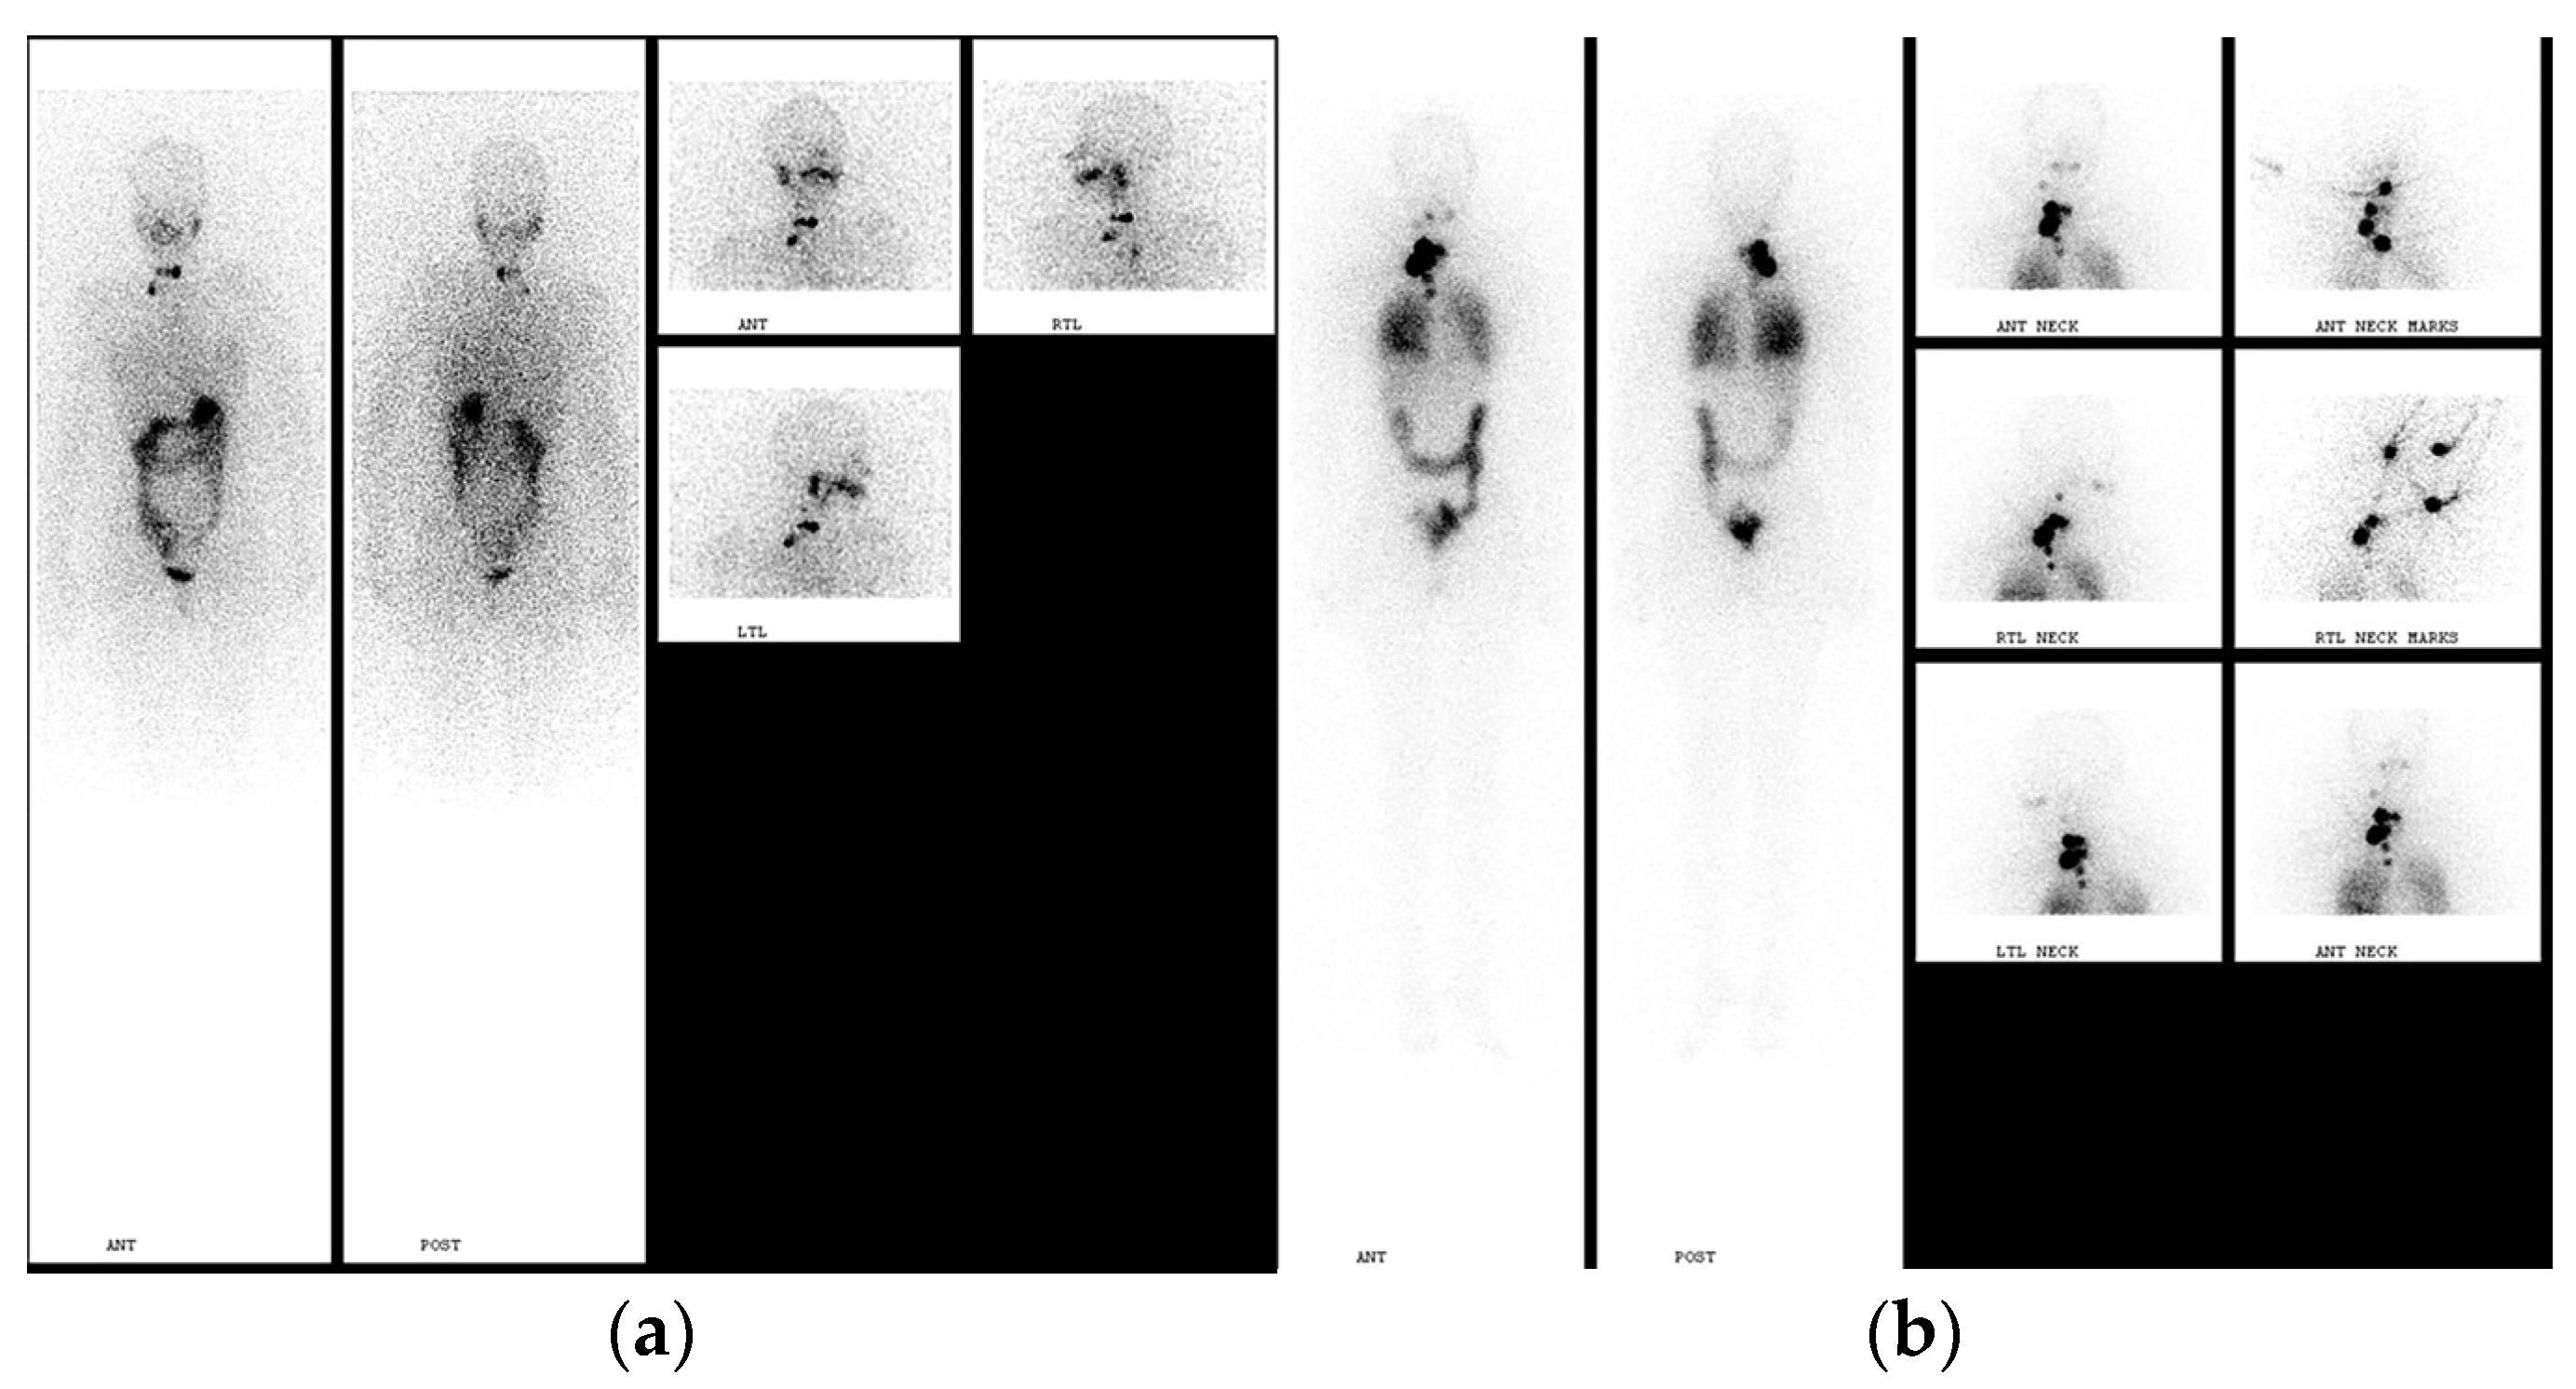

2. Pre-Treatment Whole-Body Imaging

3. Post-Treatment Whole-Body Imaging